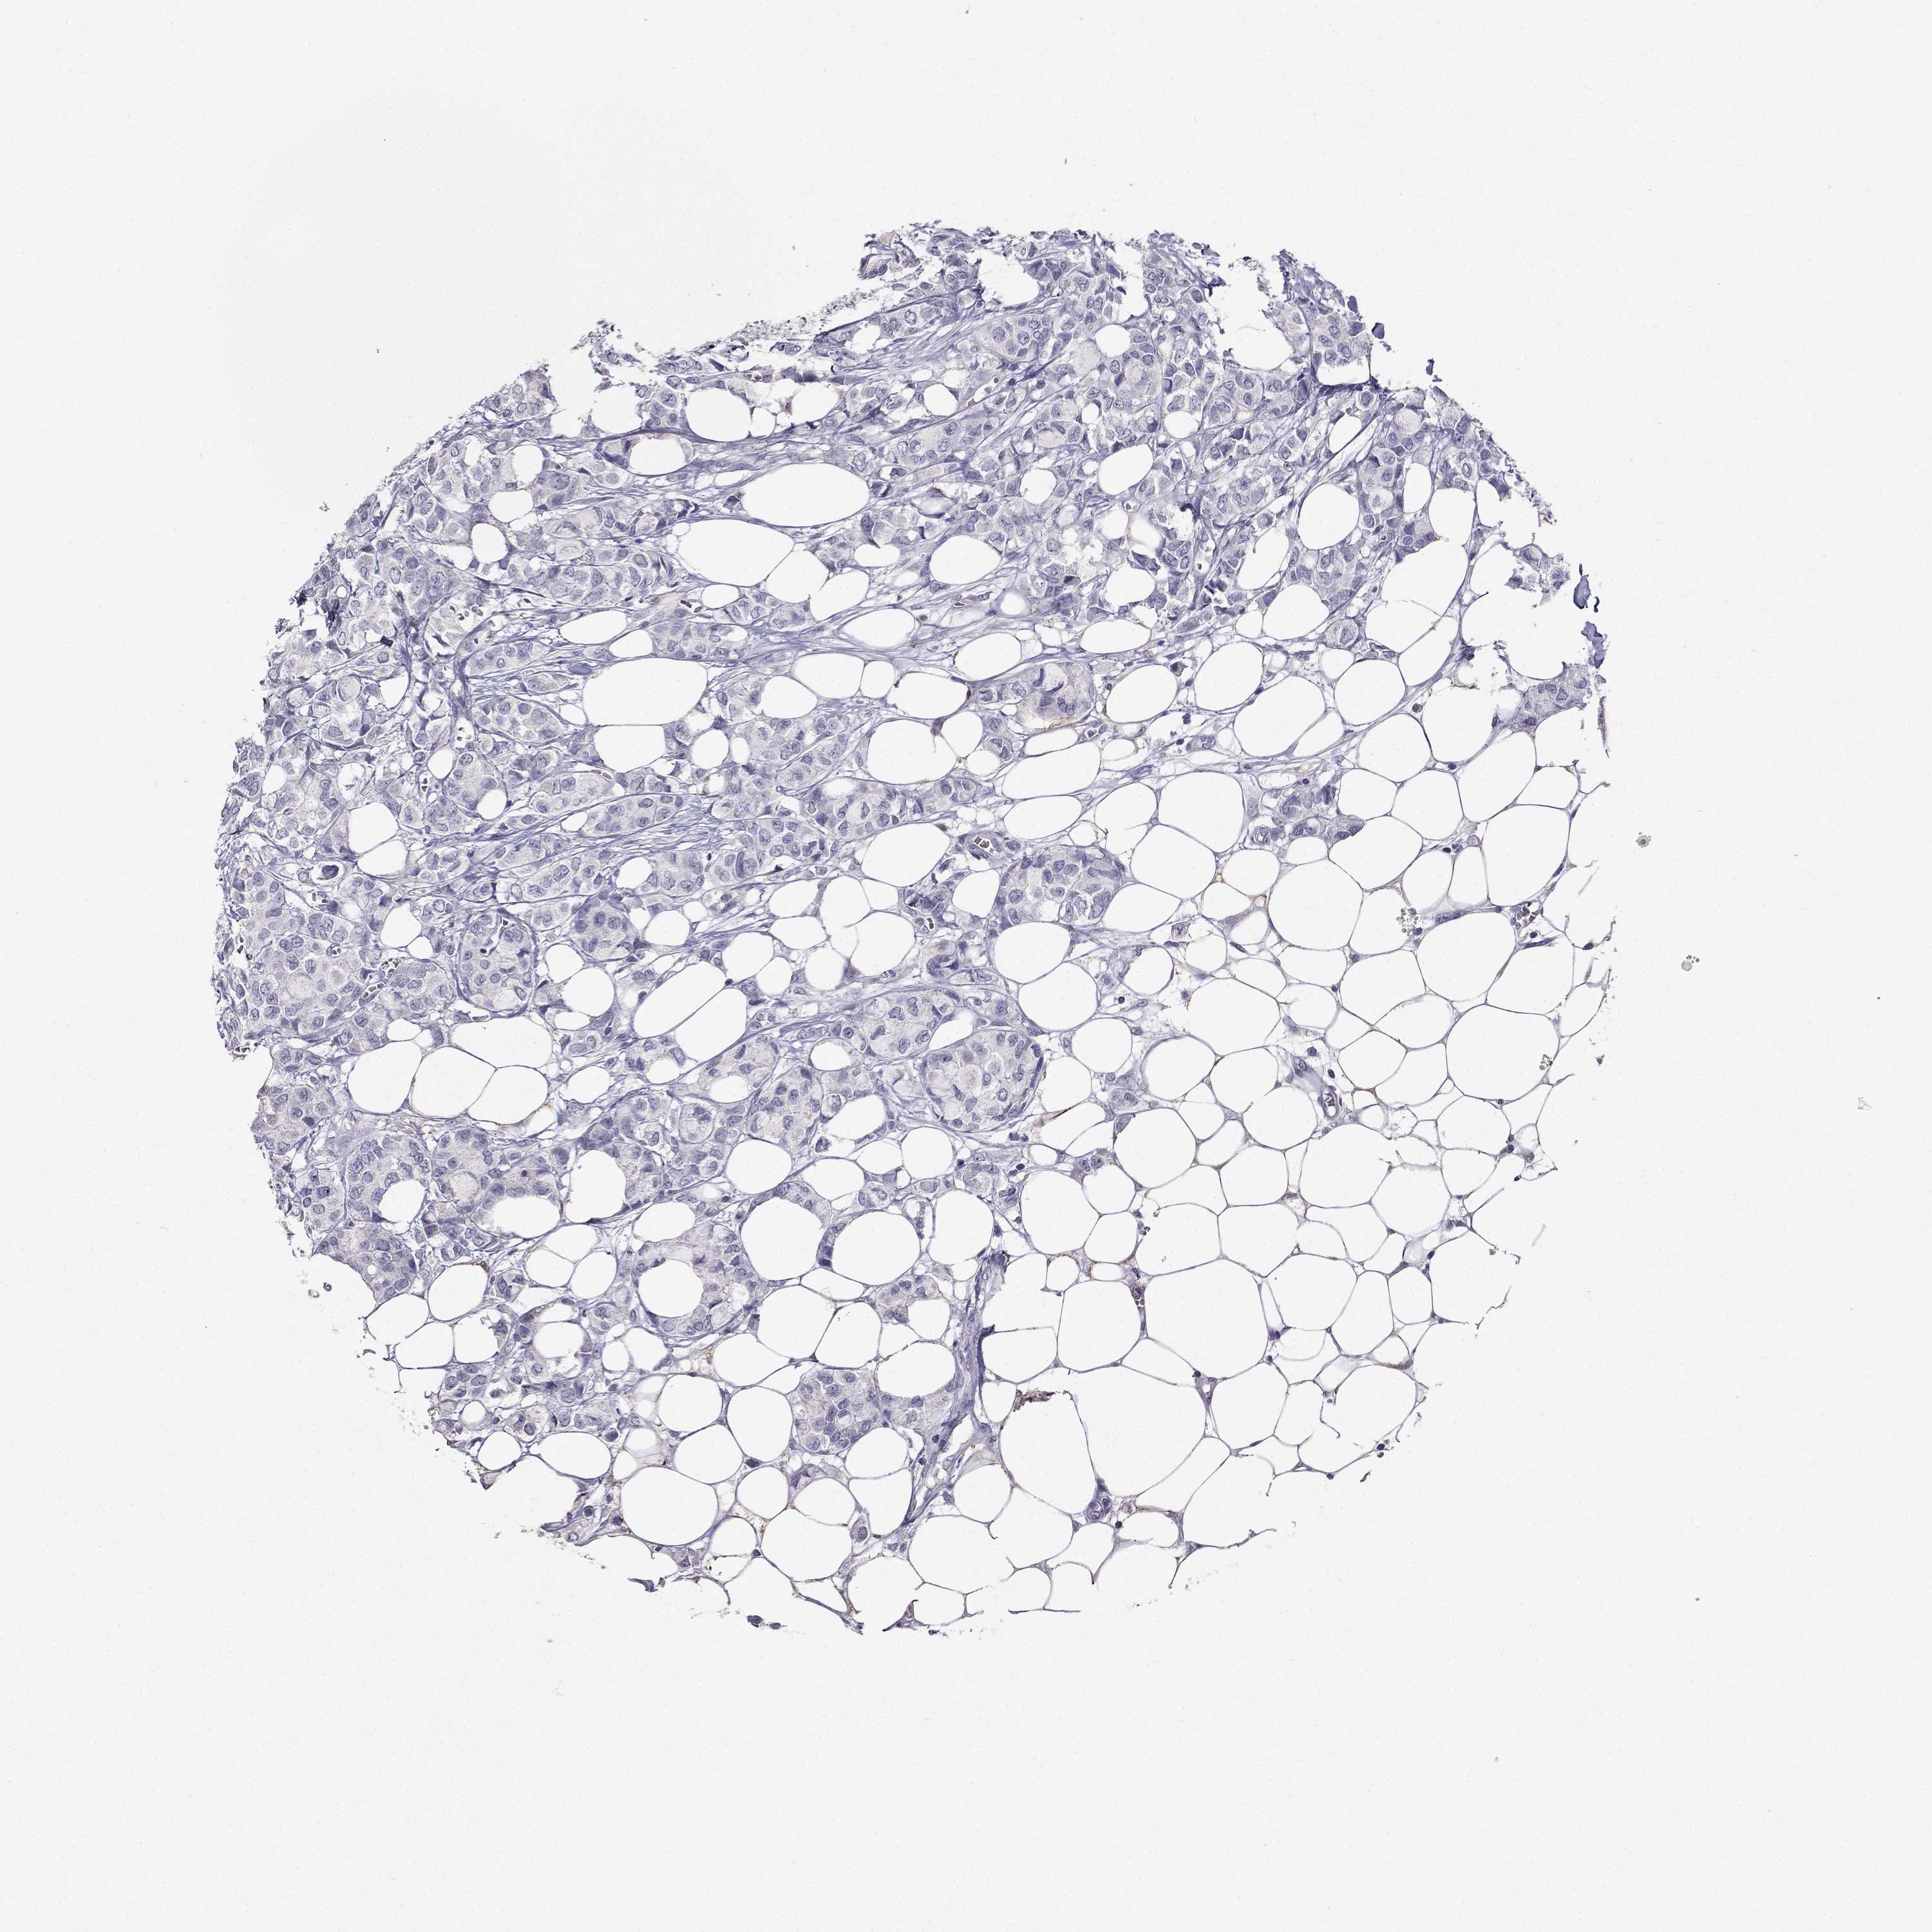

CANCER BREAST CANCER Show tissue menu

BRCA TCGA BRCA VALIDATION PROTEIN EXPRESSION